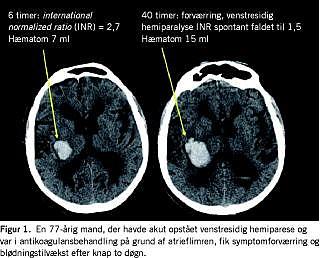

Patofysiologi og risikofaktorer

Afhængigt af den underliggende årsag opdeles ICH i primær, som udgør ca. 85%, og sekundær, som udgør ca. 15% af tilfældene (Tabel 1 ). Primær ICH er oftest associeret med hypertension (> 50%) eller cerebral amyloid angiopati (> 30%) [1, 2]. Kronisk hypertension medfører degeneration, fragmentering og fibrinoid nekrose af især små penetrerende arterier, som dermed lettere brister [3]. Hypertensionsblødninger er derfor typisk beliggende dybt i hjernen i perforantarterier fra arteria cerebri media og arteria basilaris. Cerebral amyloid angiopati ses oftest hos ældre patienter, og blødningerne er som regel lokaliseret mere overfladisk (lobære blødninger). Der kan forekomme flere blødninger samtidig, og recidiv-ICH ses hos 5-15% pr. år. Diagnosen kan dog først stilles med sikkerhed post mortem. Billeddiagnostiske studier med gentagne undersøgelser det første døgn efter ictus har i de senere år givet ny viden om patofysiologien ved primær ICH. En hæmatomtilvækst på mere end en tredjedel af volumen forekommer især i de første tre timer (hos 40%), men forekommer hos 73% af alle ICH-patienter inden for det første døgn (Figur 1 ) [4, 5]. Rundt om den primære blødning udvikles der efter det første døgn ødem og neuronskade som primært skyldes inflammation forårsaget af hæmatomet og ikke som tidligere antaget en iskæmisk penumbra [6].